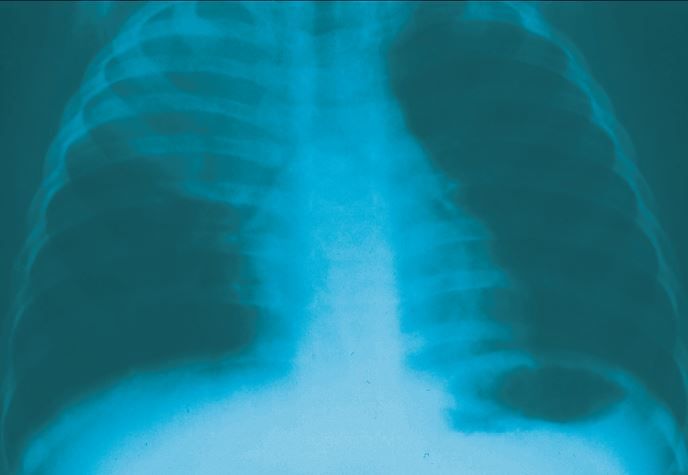

Right upper lobe consolidation is evident in this chest x-ray film from a 2-year-old girl who had an abrupt onset of fever, chills, productive cough, and abdominal pain. Based on her workup and response to therapy, the diagnosis was streptococcal pneumonia.